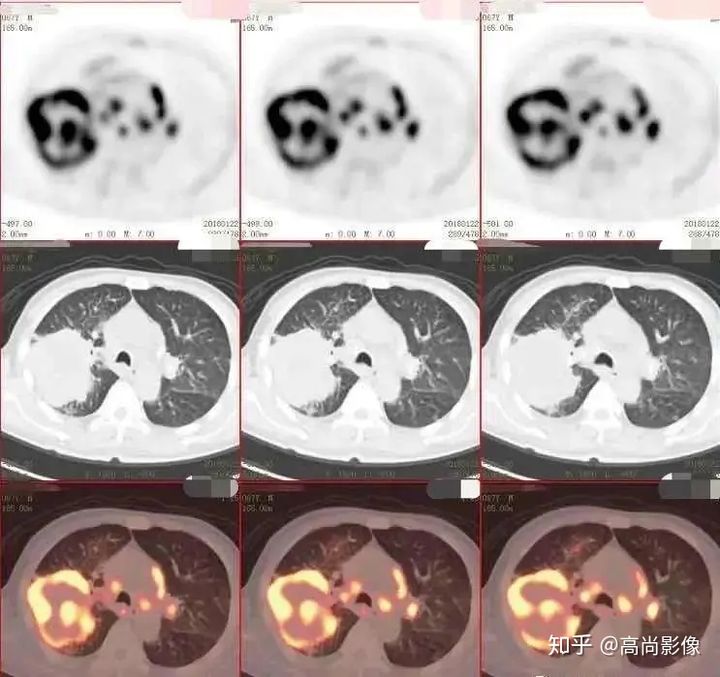

(右肺癌全身多發(fā)轉(zhuǎn)移)

(右肺上葉中央型肺癌)